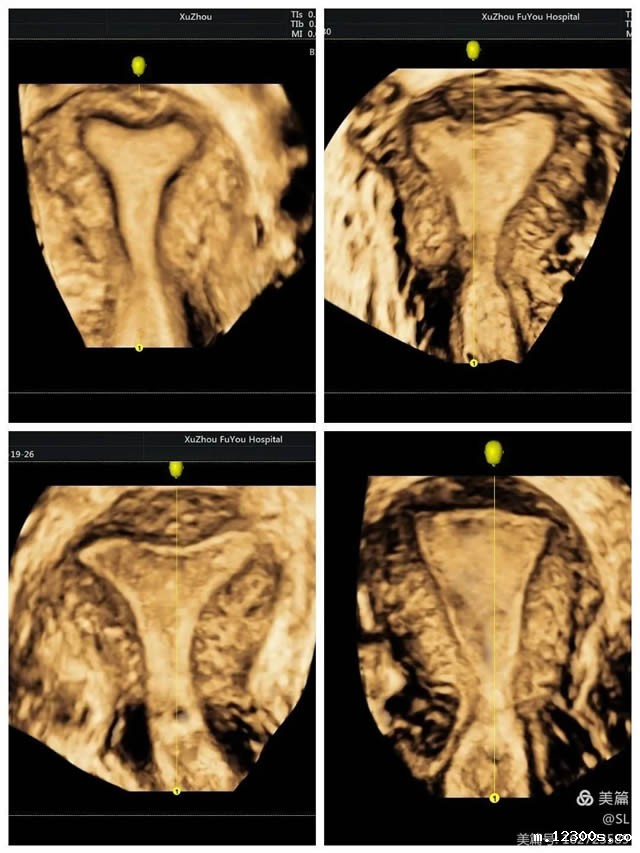

立体成像安全无创

据张丽主任介绍,经阴道三维彩超是使用容积探头对宫腔内的病变及盆腔进行三维成像,可多模式重建成像,全方位、多视角完整、立体显示宫腔内部结构和空间位置关系,直观清晰的立体成像对妇科疾病的诊断更加准确,在妇科检查中得到广泛应用。

先天性子宫畸形是妇科的常见疾病,也是女性不孕不育、习惯性流产、胎儿宫内发育迟缓等疾病的主要原因之一。经阴道三维彩超在评估子宫病变等方面,提供了更丰富的影像信息。这种超声技术不仅能够更好的观察子宫外形轮廓及宫腔内膜的形态,还能清晰观察患者宫腔内的可疑部位和周围组织,帮助医生更准确的分析判断病情。

张丽主任提到,经阴道三维超声是在二维超声基础上技术升级的检查手段。二维超声是断层扫查,很难显示冠状切面,三维超声可以立体实时、从多个面来观察,提供比二维超声更丰富的信息量,因此医生根据三维彩超来诊断,结果会更加准确。